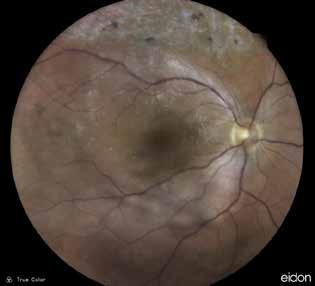

MNV may also develop in patients with central serous chorioretinopathy. In this condition, the pathogenesis of MNV is not yet fully understood. It is known that it can occur after laser photocoagulation or photodynamic therapy as a compensatory response to treatment; however, MNV may also develop in cases without history of laser treatment. In these cases, MNV may develop in a manner similar to AMD, where the rupture of Bruch’s membrane due to chronic RPE changes and long-standing serous pigment epithelium detachment allows for the growth of Type 1 neovascularization.33–36 (Figure 6)

Figure 6. Multimodal imaging of Type 1 macular neovascularization secondary to central serous chorioretinopathy. Fluorescein angiography (A and B) showing pinpoints of hyperfluorescence with leakage in the late phase. Indocyanine green angiography (C and D) displaying the central hyperfluorescent area and the adiacent area of choridal hyperpermeability. Fundus autofluorescence (E) revealing abnormalities of retinal pigment epithelium. The en face of optical coherence tomography angiography (F) showing the neovascular network and the B-scan displaying the shallow irregular retinal pigment epithelium elevation with subretinal fluid (G).